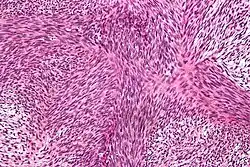

![]() Fotografía microscópica de un fibrosarcoma | ||

El fibrosarcoma es un tipo de tumor maligno que pertenece al grupo de los sarcomas. Se origina generalmente en los extremos de los huesos largos de los miembros.[1] Existe una forma de presentación infantil que afecta generalmente a niños de menos de un año y suele ser de crecimiento lento.[2] La forma del adulto en cambio se presenta a edades más avanzadas y tiende a ser de mayor agresividad. Las células que componen el tumor derivan de fibroblastos del tejido conectivo de sostén de la cavidad medular del hueso y con menos frecuencia de la parte más externa del mismo o periostio, en ocasiones surge de las partes blandas próximas al hueso. Es un tipo de cáncer muy inusual en la especie humana, se presenta por término medio un caso al año por cada 2.000.000 de habitantes.[3]